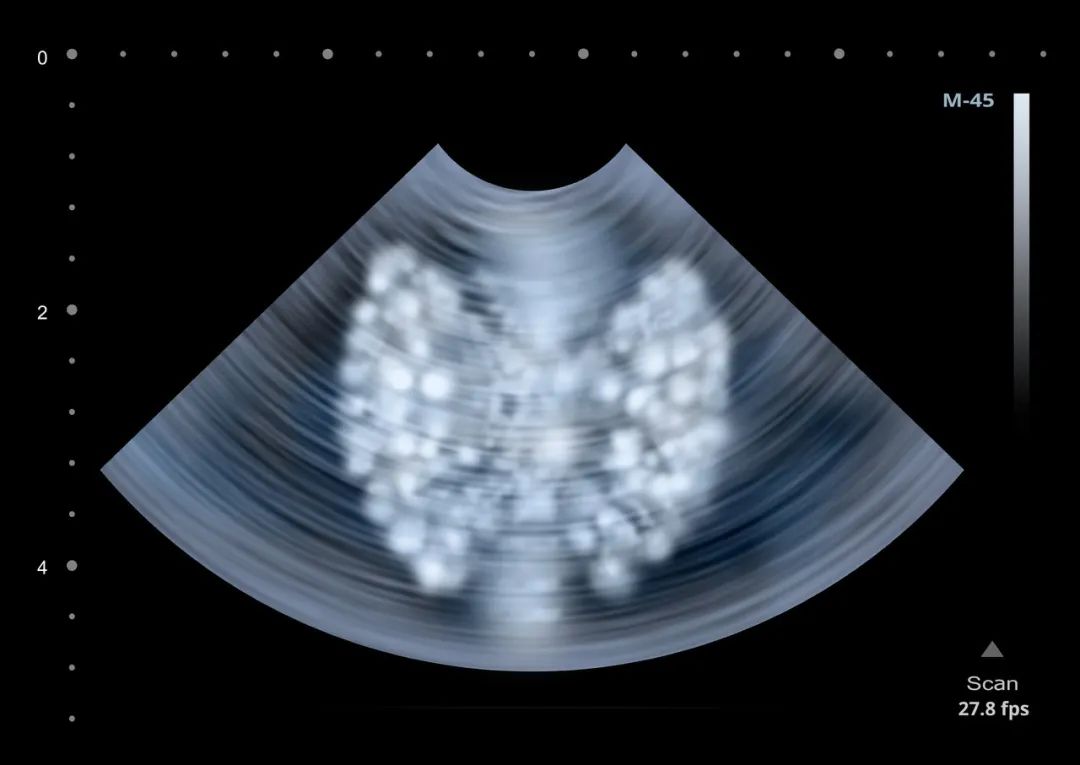

◎ 甲状腺超声检查扫描图。/ 123rf中国医师协会外科分会甲状腺外科专业常务委员兼副秘书长杨晓东接受媒体采访时,指出要客观地看待”过度诊断“的现象。